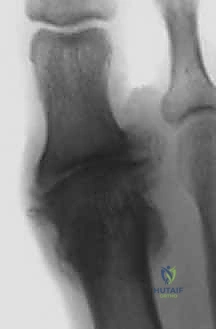

- التصوير بالأشعة السينية (X-rays): تُجرى بوضعيات الوقوف (تحمل الوزن) لتقييم درجة تآكل الغضروف، حجم النتوءات العظمية، والمحاذاة العامة للقدم.

| المرحلة 3 | تضيق شديد في مسافة المفصل، نتوءات كبيرة، تكيسات عظمية. | ألم شديد ومستمر، فقدان شبه كامل لحركة المفصل، ألم عند اللمس. | تثبيت مفصل إبهام القدم الكبير (Arthrodesis) كخيار أول. |

| المرحلة 4 | احتكاك عظم بعظم بالكامل، دمار شامل للمفصل. | ألم مبرح حتى أثناء الراحة، تشوه في المفصل، عجز عن المشي الطبيعي. | تثبيت مفصل إبهام القدم الكبير (Arthrodesis) (الحل الجذري الوحيد). |